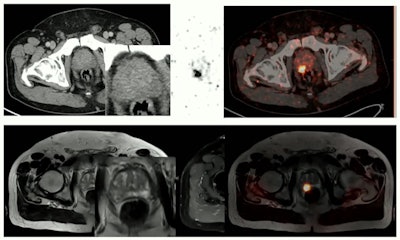

In Essen, PET/MRI is used most robustly in oncologic imaging, specifically prostate imaging. PET/CT can and is used effectively for detecting biochemical recurrence after prostatectomy, but prior to surgery, PET/MRI is superior for detecting primary tumors as well as cancer that has spread to surrounding tissue.

"This is one of the clearest application fields actually for PET/MR," Umutlu pointed out.

PET/MRI is significantly more effective than PET/CT for imaging prostate cancer prior to surgery, Umutlu said.

PET/MRI is significantly more effective than PET/CT for imaging prostate cancer prior to surgery, Umutlu said.In addition, PET/MRI is being applied successfully in soft-tissue sarcoma imaging, neuroendocrine tumor imaging (gallium-68 DOTATOC-PET/MRI), and in whole-body staging, where PET/MRI is equal to PET/CT in terms of tumor detection and acquisition times, yet holds an edge in classifying additional findings that may be indeterminate of PET/CT.